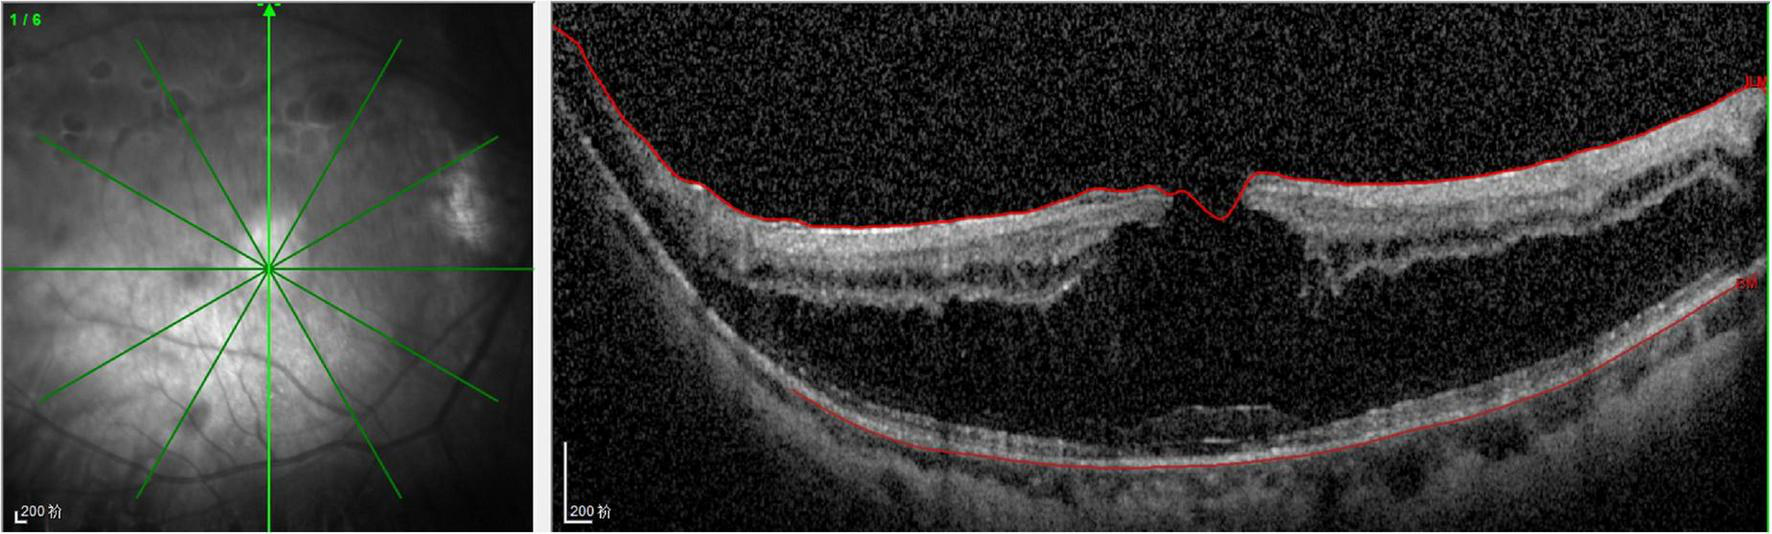

FIGURE 3

Spectral-domain optical coherence tomography (SD-OCT) revealed the lamellar macular hole and retinoschisis in her right eye.

On examination, her height and weight were 165 cm and 66.2 kg, respectively. The best-corrected visual acuity was 20/300 OD and 20/250 OS, with a refractive status of +5.25/−2.75 × 25 OD and +5.75/−3.25 × 154 OS. The anterior segment showed the absence of lenses in both eyes. Fundus examination revealed optic atrophy, staphyloma, and chorioretinal atrophy. The initial intraocular pressure was 16 mm Hg OD and 17 mm Hg OS, and the axial length was 31.11 mm OD and 29.33 mm OS. B-ultrasound showed that the lenses were located in the vitreous cavity in both eyes (red arrows, Figure 1). Orbital computed tomography (CT) demonstrated free-floating lenses in the posterior poles (yellow arrows, Figure 2), and spectral-domain optical coherence tomography (SD-OCT) revealed a lamellar macular hole and retinoschisis in the right eye (Figure 3).

Myopia is secondary to lens instability and axial elongation in patients with homocysteinemia. Previous reports have documented that high myopia is related to pathological changes in weak scleral connective tissue, and it was present in almost 45% of homocystinuria cases (4). Hsia et al. suggested that a lamellar macular hole in association with retinoschisis is specific to myopic tractional maculopathy (9). In the present case, a lamellar macular hole and retinoschisis secondary to high myopia were observed on SD-OCT images. A lamellar macular hole is a common macular structural defect in high myopia tractional maculopathy; however, its formation is complicated. Lamellar hole-associated epiretinal proliferation and posterior vitreous adhesion occur more frequently in eyes with high myopia (10).